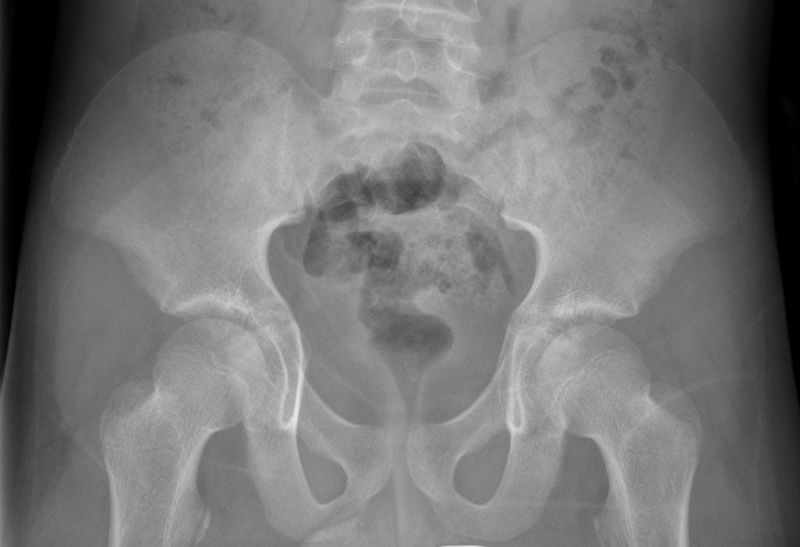

Which chromosomal abnormality shows this characteristic pelvis on imaging? (note: the pelvis has an appearance of a Disney character) A. Down's syndrome B. Turner's syndrome C. Edward's syndrome D. Patau syndrome

The answer is A. Down's syndrome. The characteristic feature of pelvis here is that the iliac crest is in the shape of Mickey mouse's ears and hence called the Mickey mouse pelvis. This kind of pelvis can also be found in cases of Anencephaly and progressive supranuclear palsy.